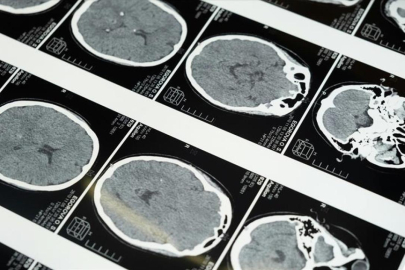

İstanbul'da düzenlenen 1. Dünya Girişimsel Nöroloji ve Nöroşirürji Kongresi'nin (WINNC 2025) düzenleme komitesinde yer alan Eskişehir Osmangazi Üniversitesi Tıp Fakültesi Nöroloji Ana Bilim Dalı Öğretim Üyesi ve İnme Merkezi Sorumlusu Prof. Dr. Atilla Özcan Özdemir, inmenin beyin damarlarının tıkanması (iskemik) ve beyin kanaması şeklinde gelişen iki türünün olduğunu söyledi.

İskemik inmenin dünyada ve Türkiye’de sık görüldüğünü, özellikle kadınlarda görülme sıklığının arttığını ve meme kanserinden daha yaygın hale geldiğini belirten Özdemir, inmenin başlıca ölüm nedenlerinden biri olduğunu ve erişkin yaşta kazanılmış engelliliğin en sık nedeni olması nedeniyle ciddi bir halk sağlığı sorunu haline geldiğini kaydetti.